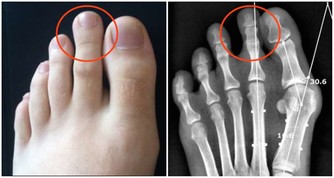

飲酒引起的癌症類型也很多,比如乳腺癌、結直腸癌、肝癌、食管癌、胃癌和胰腺癌等都有直接關係。當然,和酒關係最密切的癌症類型,還有口腔癌,喉癌,食管癌等。

中國人喝酒,更容易致癌

中國人有酒精代謝基因的缺陷。

酒精(乙醇)進入體內後,由乙醇脫氫酶代謝為乙醛,然後再由乙醛脫氫酶代謝為乙酸排出體外。中間代謝產物乙醛,是明確的致癌物。

中國人喝酒往往更容易上臉,有的人甚至吃酒心巧克力都會小臉紅撲撲的。

這是因為攜帶有突變的乙醛脫氫酶基因,導致人體無法有效降解乙醛,乙醛在體內積累後能導致血管舒張。而乙醛脫氫酶基因缺陷的人喝酒後,患癌概率會大於沒有缺陷的人。